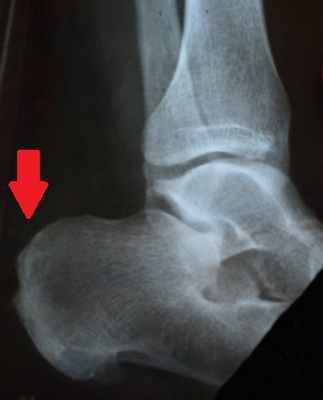

Уточнить диагноз позволяет рентгенография стопы. При этом на рентгенограмме виден костный нарост.

После консультации диагноз «пяточная шпора» подтвердился – на рентгеновском снимке костный нарост был четко виден. На приеме специалисты клиники объяснили женщине: методы, на которые она возлагала надежды, эффективны только в самом начале заболевания. А так как Наталье Борисовне пяточная шпора не один год мешает нормально жить, операция была единственным верным решением. Более того, медлить с вмешательством было ни в коем случае нельзя.

Ренген-снимок до операции Рентген стопы после операции

Диагностикой и лечением пяточной шпоры занимается врач ортопед. Основным способом выявить патологию и оценить степень ее развития является рентгенография. На снимке хорошо виден костный нарост, его форма, расположение и величина.

После изучения истории болезни, жалоб пациента, врач проводит осмотр ноги: наличие высокого свода, площадь болезненности в области пятки, наличие ограничений подвижности в стопе. Для верификации диагноза могут потребоваться инструментальные методы исследования. Рентгенография позволяет получить четкое изображение костных тканей. Это метод исследования дает возможность исключить другие причины болей в пятке,такие как перелом или артроз. Пяточная шпора хорошо визуализируется при рентгенографии.